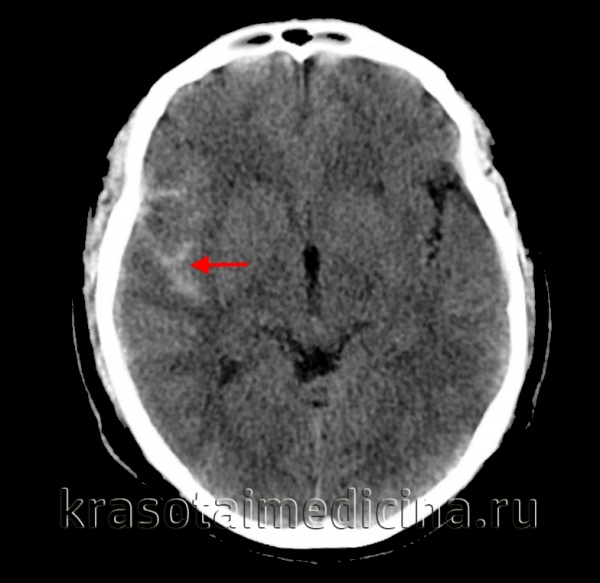

(а) MPT, Т1 -ВИ, аксиальный срез: у этой же пациентки в бороздах конвекситальной поверхности правого полушария определяется «грязный» ликвор (по сравнению с нормальной гипоинтенсивной СМЖ в контрлатеральных бороздах).

(б) MPT, FLAIR, аксиальный срез: у того же пациента в области борозд конвекситальной поверхности правого полушария определяется гиперинтенсивный сигнал (в противоположность гипоинтенсивному подавленному сигна лу от нормальной СМЖ в области борозд конвекситальной поверхности левого полушария).

Постнатально по результатам ЦСА была диагностирована васкулопатия (снимки не представлены).

о Замещение СМЖ в области борозд конвекситальной поверхности головного мозга изоинтенсивной жидкостью («грязная СМЖ»)

о Гиперинтенсивный сигнал от ликвора борозд на FLAIR

о GRE, SWI: участки «выцветания» изображения в области борозд